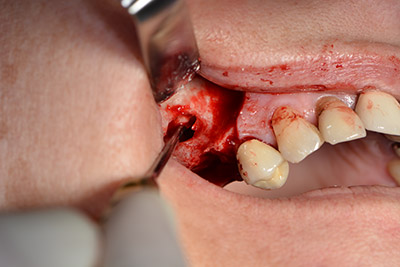

L'incisione classica (rilascio crestale e buccale) e la preparazione del lembo mucoperiosteo favoriscono un'ottima panoramica.

Quindi, abbiamo optato per il rialzo del pavimento sinusale con impianto simultaneo. Implantmed è preimpostato sulla prima posizione per quanto riguarda la fenestrazione buccale della parete del seno mascellare.

La fenestrazione è impostata su 35.000 rpm, mentre la mucosa nasale viene preparata in direzione craniale (da fig. 13 a 14).

Dunque, l'impianto viene posizionato e l'osso ricostruito. In questo caso, considerate le dimensioni della regione di accrescimento, i microframmenti dell'osso autologo (raccolti con un'apposita cannula di aspirazione in seguito alla perforazione dell'impianto 16 e della fenestrazione 14) vengono combinati con dei materiali di riempimento dell'osso.

Una membrana riassorbibile viene usata come barriera in direzione buccale per contenere l'accrescimento. Infine, vengono applicate suture resistenti alla saliva (da fig. 15 a 19).